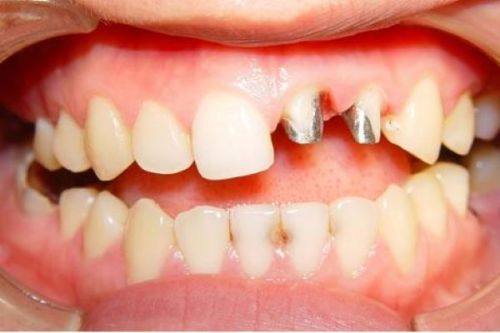

部分早期使用的烤瓷牙可能含有铁磁性金属。这类材质在强磁场环境中就像一个调皮的孩子,可能会发生位移或产热。所以,如果你的烤瓷牙是早期安装的,更好提前通过口腔X光片确认一下材质,这样才能确保检查的安心。